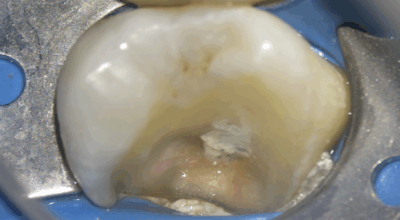

Pulpotomie camérale

Que ce soit lors du diagnostic, ou lors de l’intervention, il est possible que la pulpe camérale ne soit pas conservable. La pulpe camérale est la pulpe située dans la chambre pulpaire (schéma de gauche en rouge transparent).

A droite en jaune matériau de restauration coronaire / en gris : biomatériau bioactif (type ciment biocéramique)

Cas clinique

Pulpotomie totale : 91,3% de taux de succès